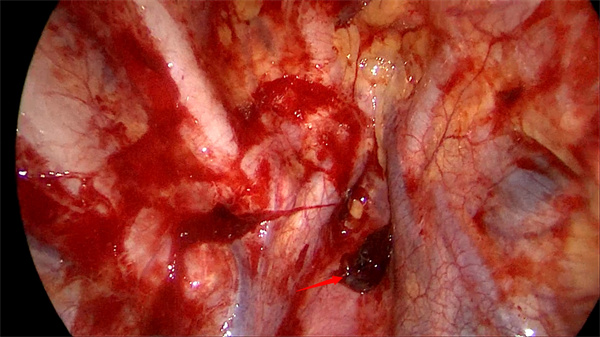

经与患者本人和家属沟通同意后,胸外科团队立即进行手术准备。迅速通知麻醉科、第一手术区紧急做术前准备。崔健会同胸外科副主任医师胡晓丹、赵云,与麻醉科、第一手术区团队共同展开抢救工作。术中,在电视胸腔镜下显示右侧胸腔大量血块,出血点为胸膜顶粘连带(图2),统计出血量达3000ml,术中血液回收机血液置换,一边输血一边进行胸腔镜下止血,右肺肺大疱切除+胸膜固定术。术后患者恢复顺利,术后第2日拔出胸腔引流管,术后第3日顺利出院。